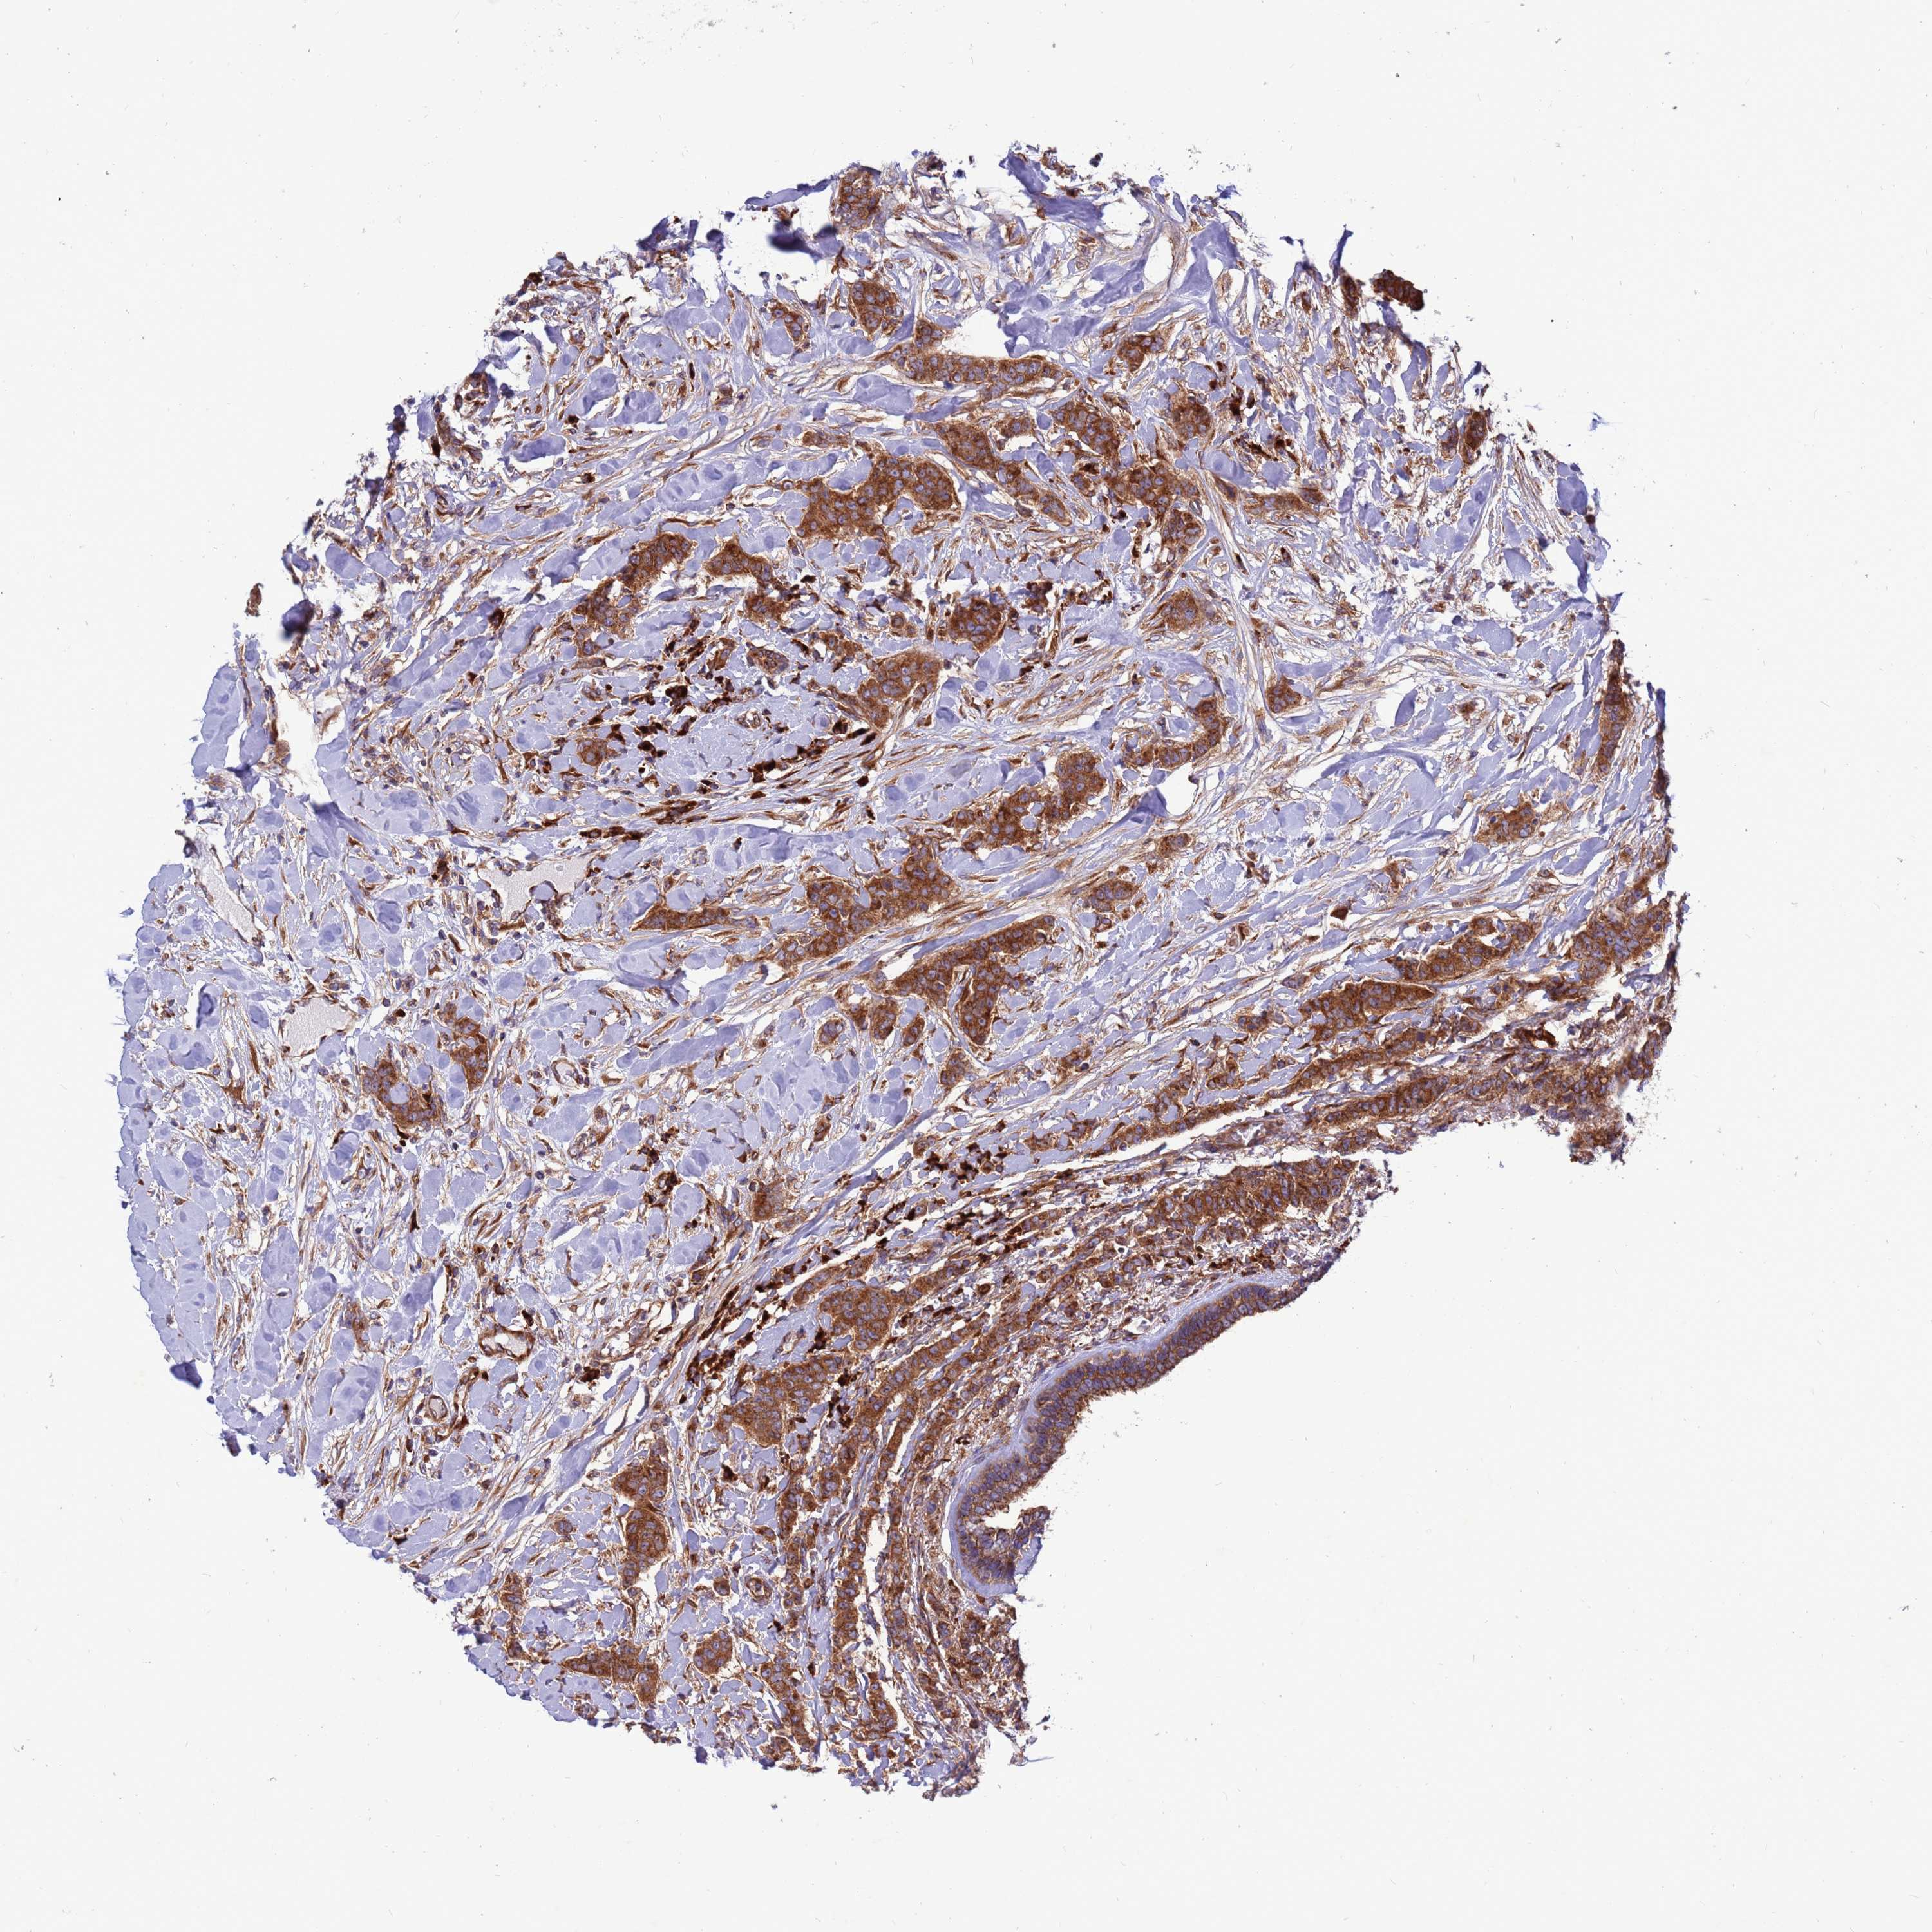

CANCER BREAST CANCER Show tissue menu

BRCA TCGA BRCA VALIDATION PROTEIN EXPRESSION